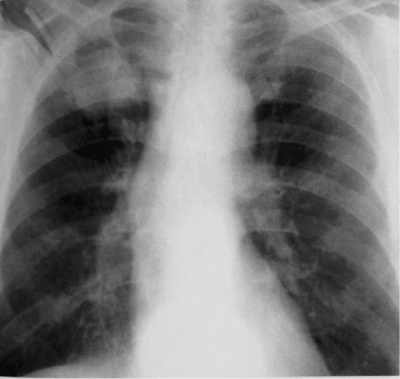

Рентгенологическая картина при туберкулёме зависит от типа и фазы развития. Чаще всего локализуется в I, II и VI сегментах лёгкого.

Затемнение при солитарной туберкулёме имеет округлую форму с чёткими и ровными контурами, средней интенсивности, при конгломератной — неправильную форму с полициклическим контуром. Контуры туберкулёмы обычно чёткие, однако их размытость указывает на перифокальную инфильтрацию, свидетельствующую о прогрессировании процесса. При этом могут наблюдаться пути к корню лёгкого в виде уплотнений по ходу сосудов и бронхов, а также очаги обсеменения. Негомогенность тени туберкулёмы объясняется неоднородностью казеозных масс: наличием фиброзных тяжей, кальцинатов и участков разрушения. В окружающей ткани часто выявляются немногочисленные полиморфные очаги и пневмофиброз[4][7].

При распаде туберкулёмы нередко образуется серповидная деструкция, расположенная у нижневнутреннего полюса. Также может появляться округлая или овальная полость в центральной части образования. В некоторых случаях распад сопровождается обильным выделением казеозных масс, что приводит к формированию каверны на месте туберкулёмы[6].